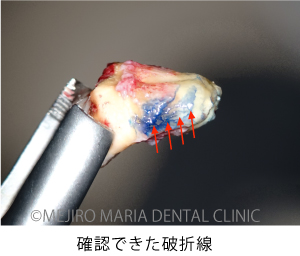

精密根管治療の開始後、根管内充填物(感染物)を除去して根管内を確認すると、歯根破折が見られました(中央写真の赤矢印)。歯根破折は根管内に留まっていましたが、歯周ポケットと繋がっていたため、1回目の治療を中止しました。

歯牙を抜歯後、メチレンブルーにて染色して破折線を確認しました。破折線に沿って感染部位を除去しましたが、根管内部の構造が非常に複雑なため、最終的な形態は、真ん中の写真のようにしました。